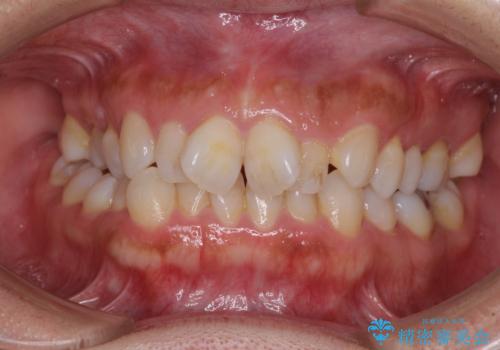

[ マウスピース矯正 ] 出っ歯に見える前歯を改善したい

![[ マウスピース矯正 ] 出っ歯に見える前歯を改善したいの症例 治療前](https://seimitsushinbi.jp/wp/wp-content/uploads/2023/10/IMG_6858-500x350.jpg?v=1697014973)